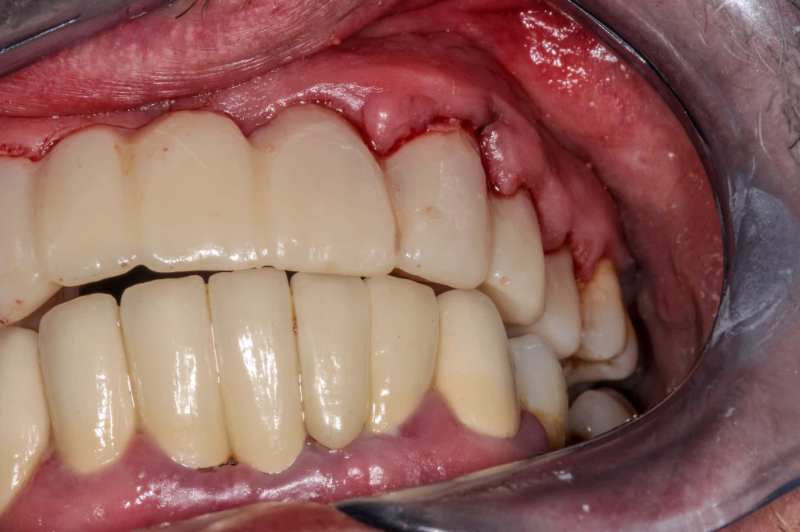

歯周ポケットが深くなり、歯周病菌の除去や清掃ができない場合には、歯茎を切開する歯周外科治療を行います。歯茎を切開して深部の歯石や歯周病菌を除去し、歯周ポケットを浅くすることで、歯周病の進行を抑えます。

歯周病の進行度合いによっては、歯茎の形を整える歯肉整形術や、歯槽骨を再生する歯周組織再生療法などの外科治療を行う場合もあります。